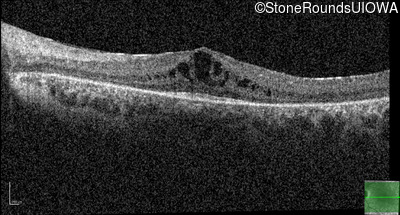

Age at visit: 7 years

OD OS

Age at visit: 8 years